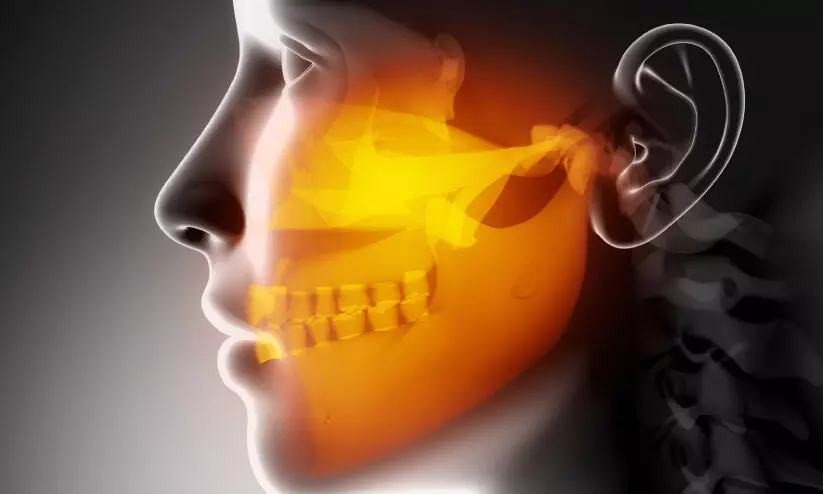

text_fieldsപ്രതീകാത്മക ചിത്രം